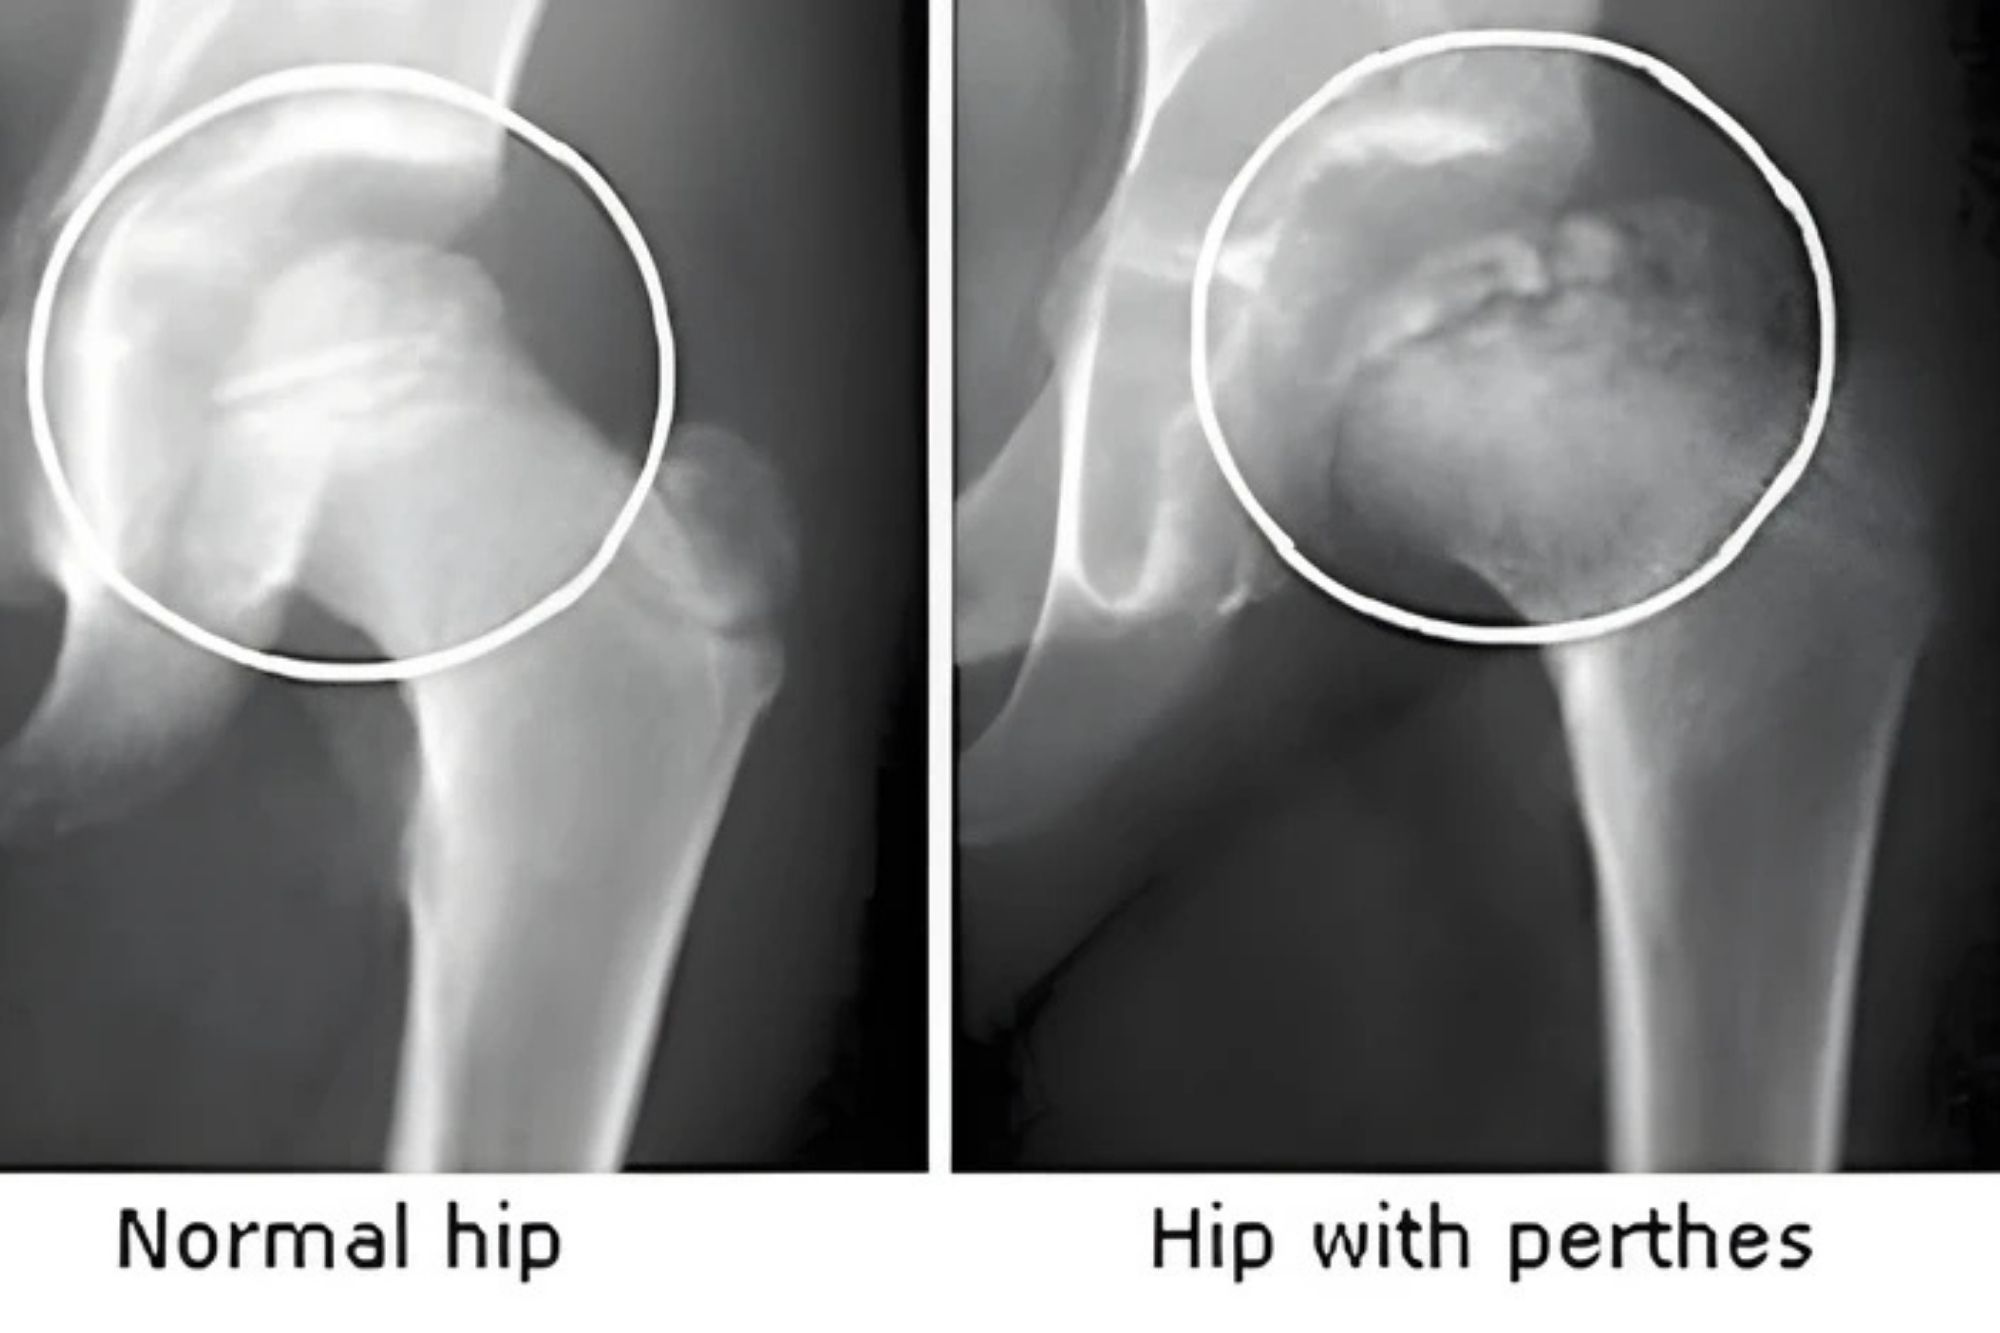

Dr. Biplab Mozumder is a highly respected and compassionate Paediatric Orthopedic Specialist in Bangladesh with over 15 years of experience in treating children’s bone and joint problems. He is known for his expertise in correcting deformities, managing complex orthopedic conditions, and applying advanced surgical techniques like Ilizarov. Parents across Bangladesh trust him because of his dedication to providing safe, reliable, and effective treatment for children.